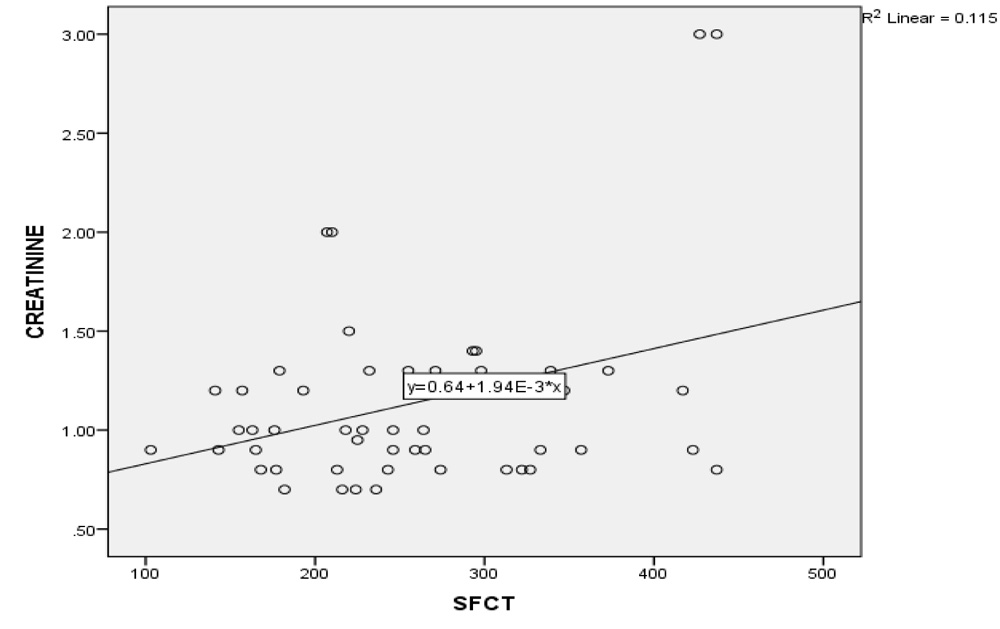

In NPDR group, there was no significant correlation between CT and creatinine (p = 0.2), urea (p = 0.17) and HbA1C levels (p = 0.71). However, in the PDR group, there was significant positive correlation between increasing levels of both creatinine & urea with SFCT (p=0.01 & p=0.04 respectively). (Table 2 and 3; Graph 1 and 2), while no correlation existed with HbA1C levels.

Graph 1: Correlation between changes in subfoveal choroidal thickness with creatinine levels in PDR group